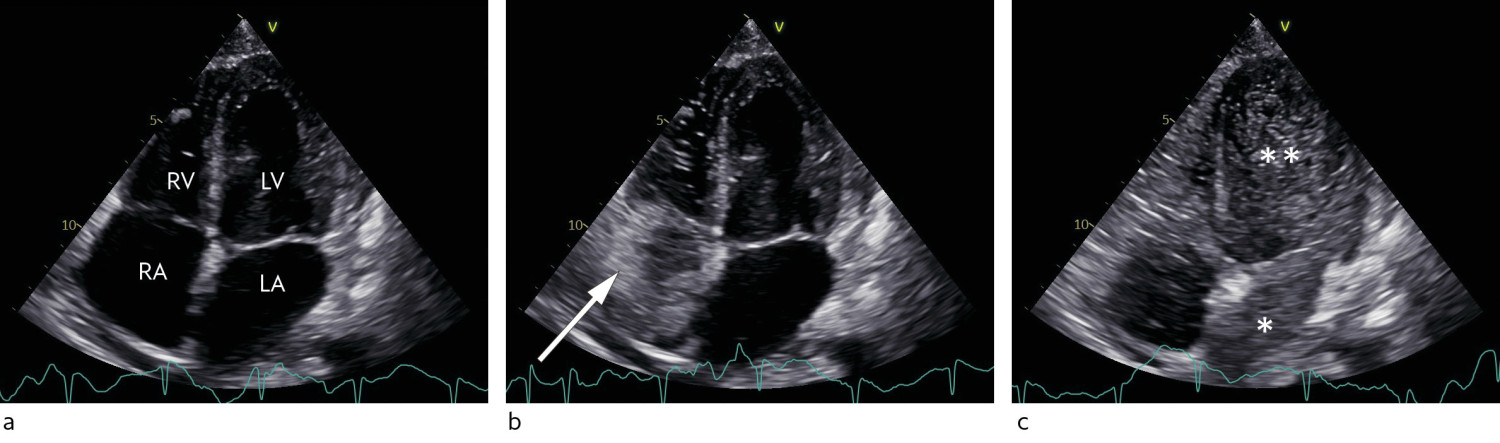

Transthoracic echocardiography (TTE) with and without agitated saline contrast (also referred to as bubble contrast) revealed normal dimensions of the left ventricle with good contraction and ejection fraction (EF) of 55 % with no significant valve defects. The right ventricle was dilated with good contraction, mild pulmonary hypertension and mild biatrial dilation. Agitated saline contrast echocardiography revealed a large atrial shunt with abundant passage of agitated saline contrast from the right to left side of the heart via the pulmonary veins after three consecutive heartbeats. This suggested a large intrapulmonary right-to-left shunt, consistent with intrapulmonary vascular dilation.

TTE with agitated saline contrast, also referred to as bubble contrast, is the first choice to evaluate right-to-left shunt because the method is less invasive than other methods (4, 5). Other methods for shunt evaluation with invasive testing are rarely necessary unless TTE with agitated saline contrast is ambiguous or unavailable, or the diagnosis is uncertain. In healthy individuals, the contrast will only fill the right heart chambers before being filtered by the pulmonary capillary bed. In patients with intrapulmonary shunt, bubble contrast will usually appear in the left side of the heart within 38 heartbeats after contrast administration (6, 7) (Figure 1) (see the video and note the saline contrast from the 13th second). Bubble contrast echocardiography can be more sensitive when performed in an upright position than a recumbent position (8).